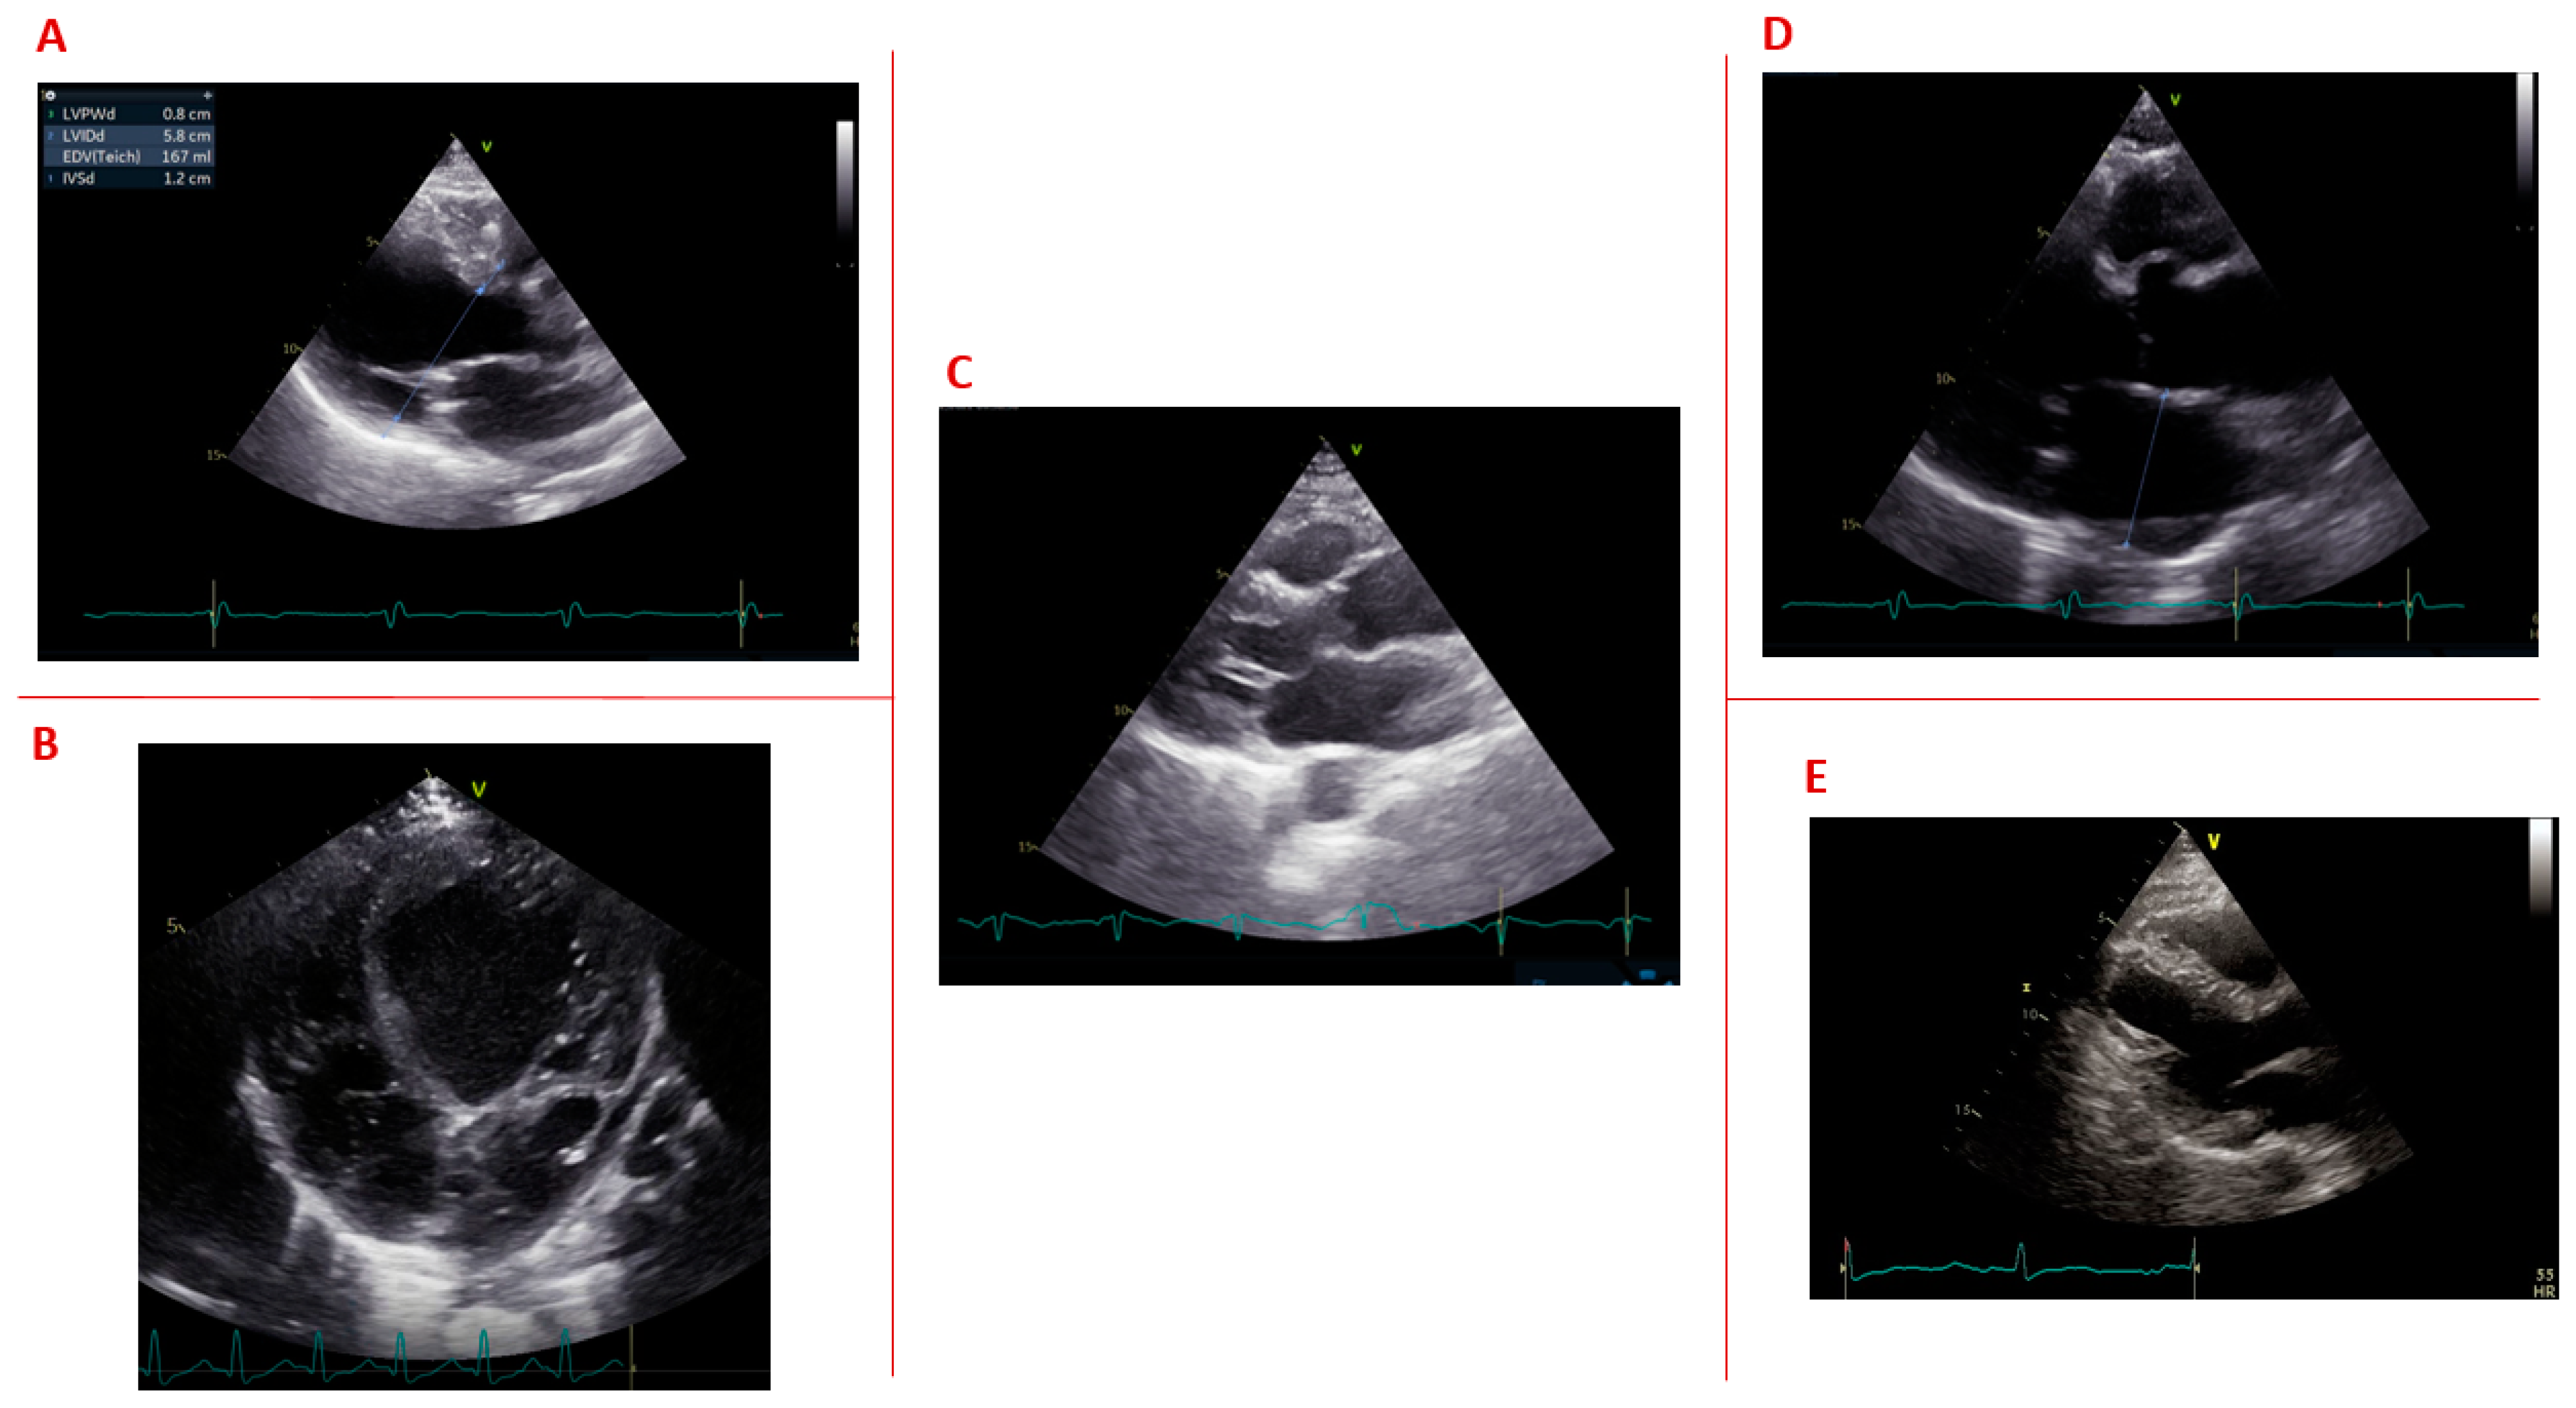

1.6. Structural Cardiac Abnormalities

- Di Cori, A.; Bongiorni, M.G.; Zucchelli, G.; Soldati, E.; Falorni, M.; Segreti, L.; Gemignani, C.; Siciliano, A.; Bovenzi, F.M.; Di Bello, V. Early left ventricular structural myocardial alterations and their relationship with functional and electrical properties of the heart in myotonic dystrophy type 1. J. Am. Soc. Echocardiogr. 2009, 22, 1173–1179. [Google Scholar] [CrossRef] [PubMed]

- Paunic, T.; Peric, S.; Cvitan, E.; Raspopovic, S.; Peric, M.; Stojmenovic, G.M.; Stojanovic, V.R. Routine echocardiography in patients with myotonic dystrophy type 1. J. Chin. Med. Assoc. 2017, 80, 408–412. [Google Scholar] [CrossRef] [PubMed]

- Choudhary, P.; Nandakumar, R.; Greig, H.; Broadhurst, P.; Dean, J.; Puranik, R.; Celermajer, D.S.; Hillis, G.S. Structural and electrical cardiac abnormalities are prevalent in asymptomatic adults with myotonic dystrophy. Heart 2016, 102, 1472–1478. [Google Scholar] [CrossRef]

- Bhakta, D.; Lowe, M.R.; Groh, W.J. Prevalence of structural cardiac abnormalities in patients with myotonic dystrophy type I. Am. Heart J. 2004, 147, 224–227. [Google Scholar] [CrossRef]

| Bhakta [48] | 2003 | Based on a prospective multicenter registry | 382 | 42.2 ± 12.3 (17.9–77.8) | - | Structural cardiac abnormalities | Structural cardiac abnormalities determined with cardiac imaging included left ventricular hypertrophy (19.8%), left ventricular dilatation (18.6%), left ventricular systolic dysfunction (14.0%), mitral valve prolapse (13.7%), regional wall motion abnormality (11.2%) and left atrial dilatation (6.3%). |